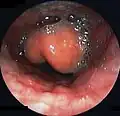

Swollen epiglottis in laryngoscopy

Diagnosis may be confirmed by direct inspection using a laryngoscope, although this may provoke airway spasm.[19] If epiglottitis is suspected, attempts to visualize the epiglottis using a tongue depressor are discouraged for this reason; therefore, diagnosis is made on basis of indirect fiberoptic laryngoscopy carried out in a controlled environment like an operating room.[19] An infected epiglottis appears swollen and is described as having a "cherry-red" appearance.[20] Imaging is rarely useful, and treatment should not be delayed for this test to be carried out.[19]

Left column: Normal epiglottis. Right column: Epiglottitis.